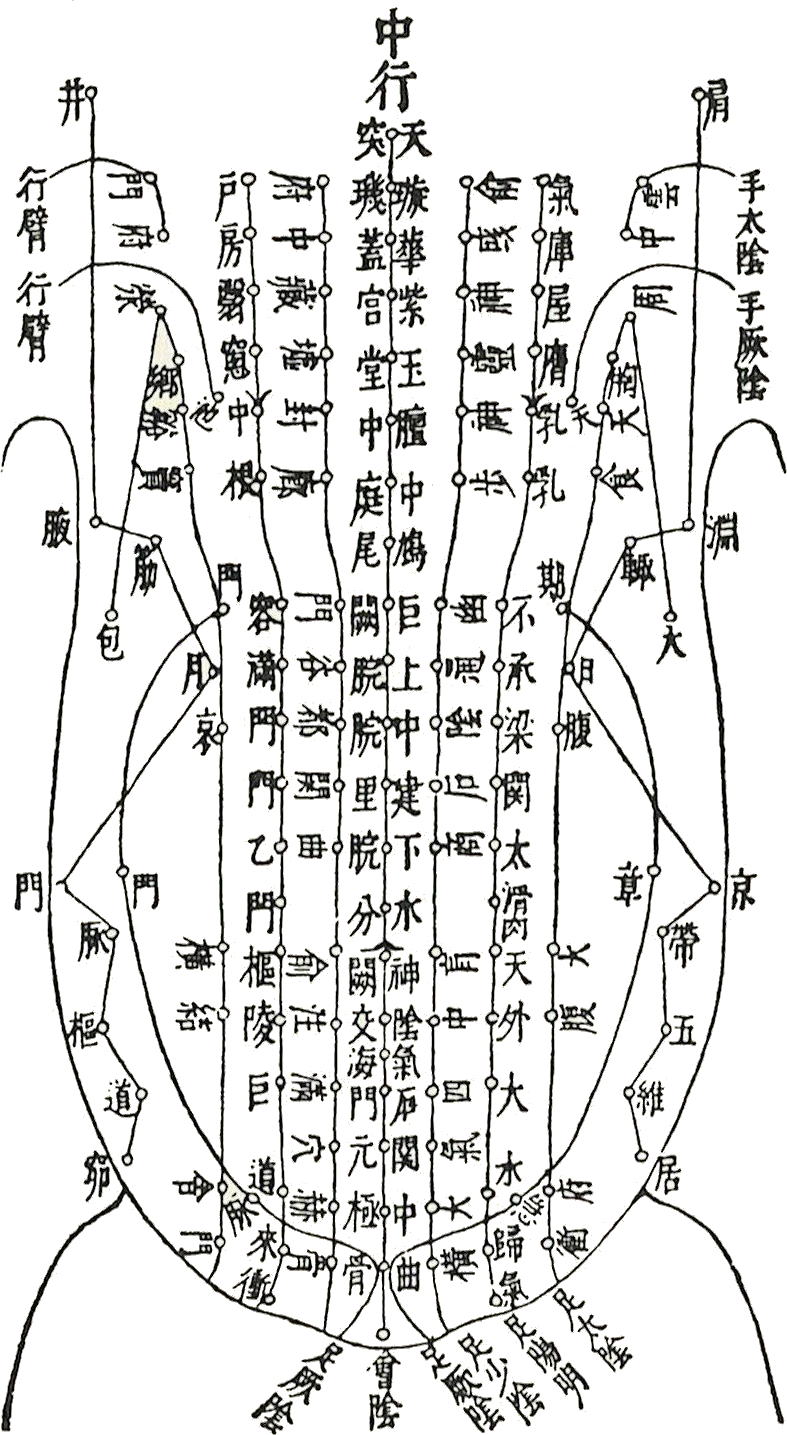

| HOME > 学習ノート> >お腹のみかた、触れ方② 腹診は先人たちのご苦労されて残されたものから、多くを学ぶことができます。 たにぐち書店の難経からお腹の経絡図をお借りして載せています。 ツボも細かく書かれていますが、お腹にはすべての経絡が関わっています。 肺経は経絡図を見ますと、表面上では胸部の一部と腕だけだと思われますが、決してそうではなく腹部の中に 入って働いていることが右の図をご覧頂くとお判り頂けるかと存じます。   また、お腹のみかたも、鍼道秘訣集、夢分の描かれたものや増永静人先生の腹部スジ反応部位をご覧頂くと、 人により観方、感じ方が異なっていることが分かるかと思います。 ではどちらを信じて学べば良いのでしょうか。 どちらの方もこの道の大家でいらっしゃいますから迷うでしょう。 答えですが、まず、どちらも覚え、頭の片隅に入れておきますが、最終的には幾度も施術をしながら自分の感覚 を信じ、答えを出すことです。 鍼道秘訣集 夢分